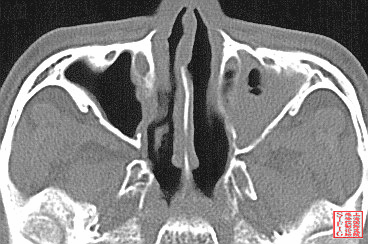

1990年RCT研究显示,鼻窦炎发生率,经鼻插管者(43.1%)显著高于经口插管(1.8%)。

Prospective RCT of 111 pts, randomized to either orotracheal or nasotracheal intubation; All had a nasogastric feeding tube. Primary outcome:  incidence of maxillary sinusitis by radiography (Waters' view) at the bedside. Maxillary sinusitis occurred in 1/53 (1.8%) of the orotracheal group (on the nasogastric tube side), and in 25/58 (43.1%) of the nasotracheal group (7 on the nasogastric tube side, 11 on the endotracheal tube side, 7 bilateral; p less than 0.001). long-term orotracheal intubation reduced significantly the incidence of maxillary sinusitis in comparison with nasotracheal intubation.